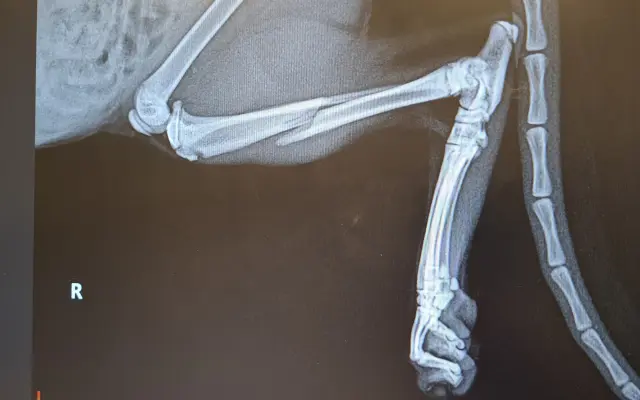

Fotogalerie